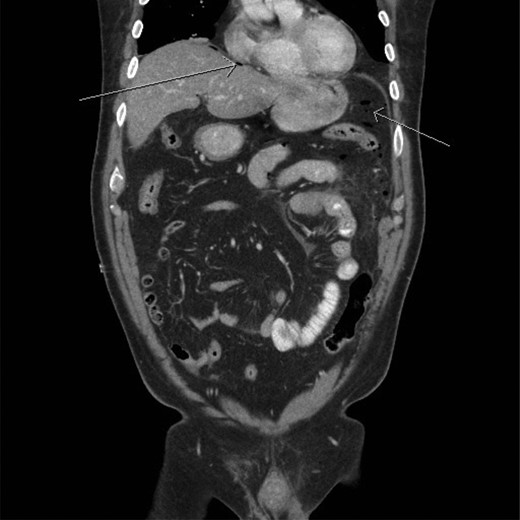

A CT scan demonstrated significant soft tissue stranding/edema of the omentum in the left hemi-abdomen. In addition, there was mild ascites and multiple scattered locules of air (Figs 3–5). No other abnormality of the small or large bowel was identified. He was admitted for observation and broad-spectrum antibiotic therapy was initiated. On post admission day 2, he became diffusely peritonitic, febrile with a temperature of 39.1°C and his oxygen requirements increased to 12 l/min.

CT scan (frontal view) demonstrating stranding/edema to the omentum (arrow).

Our case demonstrates the diagnostic dilemma that accompanies delayed bowel injuries. Laboratory tests often give nonspecific results that seldom point to a diagnosis [1]. Imaging studies also fail to establish the etiology. Our CT scan failed to demonstrate significant intraperitoneal free air (Figs 3–5). In addition, oral contrast was utilized, but gross extravasation was not identified.